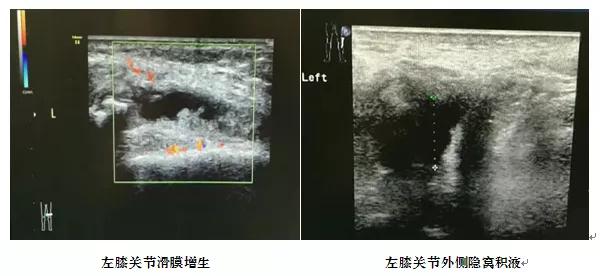

超声能探查PsA中较常见的腕、膝和跖趾关节的关节积液和滑膜炎,滑膜增生等,简便易行。